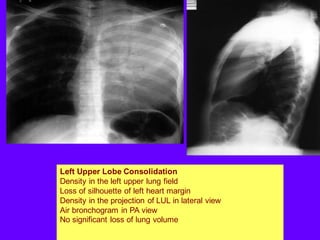

Left Upper Lobe Consolidation

Density in the left upper lung field

Loss of silhouette of left heart margin

Density in the projection of LUL in lateral view

Air bronchogram in PA view

No significant loss of lung volume